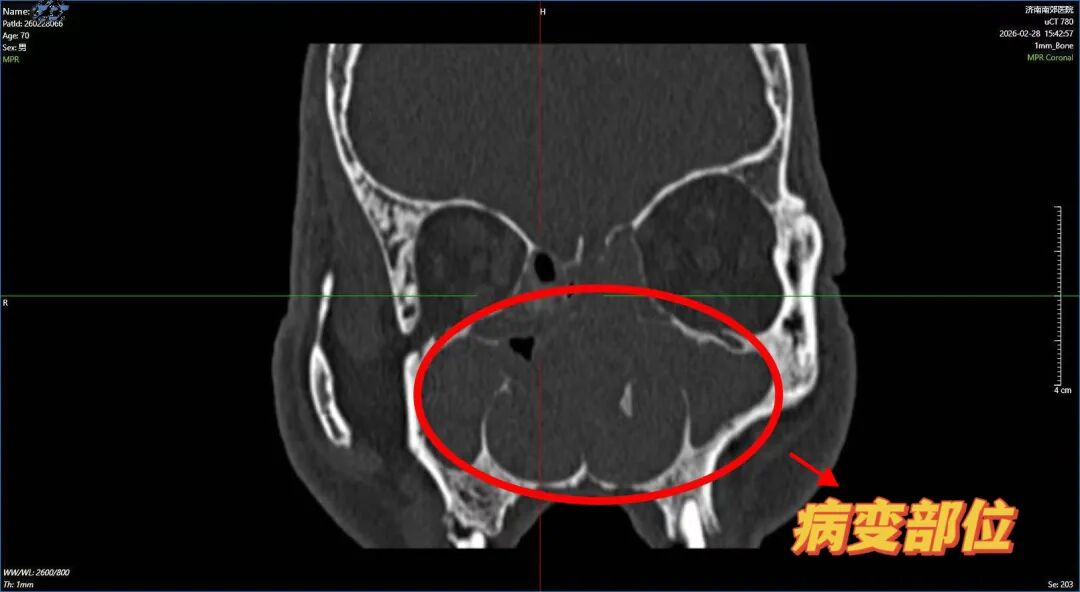

耳鼻喉科杨钦龙主任详细询问病史,结合触诊与鼻内镜检查,发现其双侧鼻腔布满息肉样组织,中鼻道及嗅裂被完全堵塞,多个鼻窦存在炎症积液,诊断为“慢性鼻窦炎伴鼻息肉、鼻中隔偏曲”。考虑到患者高龄、基础病多且长期缺氧影响全身状态,杨主任团队为其制定了“鼻内窥镜下多鼻窦开窗+鼻息肉切除”的微创方案,既能彻底清除病灶,又能最大限度保护鼻腔功能。

手术在杨主任丰富的临床经验,在鼻内镜高清视野下精准定位病变范围中精确完成。术后第二天,张大爷便觉呼吸通畅,久违的清新空气让他激动地反复摸索着说:“通了!通了!”